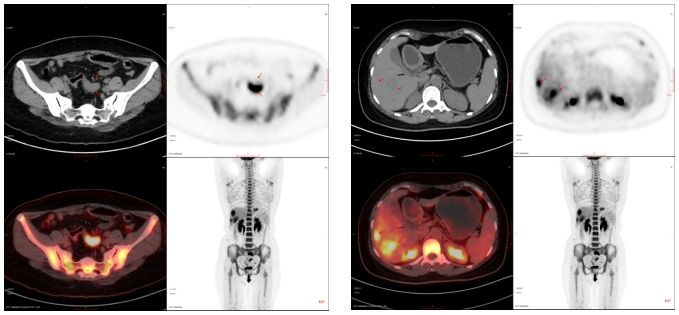

66歲,女,左側(cè)腰骶部疼痛1月,ECT檢查示:胸7、骶1及左側(cè)髂骨多發(fā)骨代謝異常,考慮腫瘤性病變,轉(zhuǎn)移瘤?

PET/CT診斷:右肺上葉后段結(jié)節(jié),代謝增高,考慮原發(fā)惡性病變(右肺上葉后段周圍型肺Ca)伴、肺內(nèi)、淋巴結(jié)及多發(fā)骨轉(zhuǎn)移。